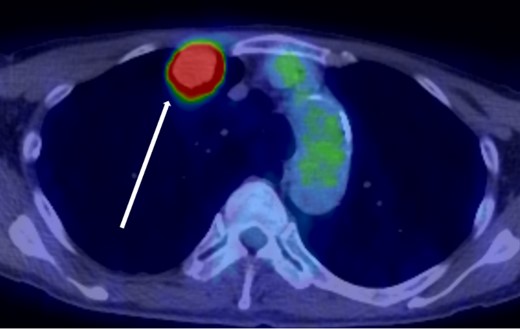

The patient was a 73-year-old man. He had a history of arteriosclerosis obliterans in the lower extremities, transient atrial fibrillation, and was consuming two antiplatelet agents. The patient had a fever within the range of 38°C. Blood tests showed an elevated white blood cell (WBC) count of 31.6 × 103/μl (neutrophil, 90.2%), CRP of 9.67 mg/dl, and APTT of 125.4 s. Chest radiography revealed an abnormal shadow in the upper lobe of the right lung (Fig. 1). Contrast-enhanced chest CT revealed an irregularly shaped mass, 43 × 33 × 28 mm in size, in the upper lobe of the right lung (Fig. 2). 18F-fluorodeoxyglucose-positron emission tomography showed abnormal accumulation with a maximum standardized uptake value of 28.4 in a pointed lesion in the upper lobe of the right lung (Fig. 3). A bronchoscopic biopsy was performed, and the patient was diagnosed with non-small cell carcinoma.

18F-fluorodeoxyglucose positron emission tomography findings. Abnormal accumulation of Max SUV 28.4 was found in a pointed lesion in the right upper lobe of the lung, which was considered to be a primary lung cancer site.